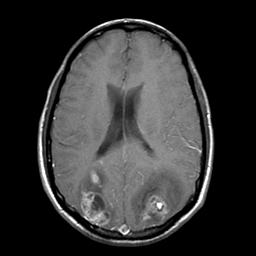

Sarcoma, MR Study #1 mr-gad -- Slice #14

[Home][Help][Clinical] Slice 14